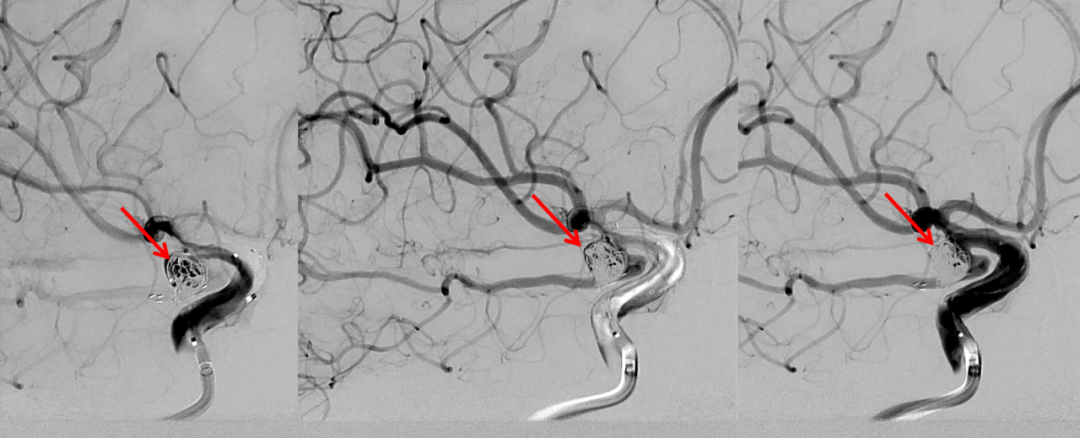

栓塞微导管到位后首先使用弹簧圈栓塞,成篮不稳定,使用Atlas支架4.0mm×21mm保护后交通动脉(箭头所示支架头端及尾端),释放支架的要点在于精准定位,同时判断微导管张力,在预设的释放起点准确打开支架,之后顺行释放支架,支架的尾端打开时须不受颈内动脉管径约束,依靠张力摆动至颈内动脉后交通动脉段远端,起到保护后交通动脉的目的。

栓塞动脉瘤:在栓塞动脉瘤过程中血管造影可见后交通动脉均显影,动脉瘤栓塞致密,术中依次使用弹簧圈:使用Target2mm×4cm、Target2mm×4cm、Target2mm×4cm栓塞子瘤,再使用多枚弹簧圈补充栓塞瘤体。

栓塞动脉瘤:在栓塞动脉瘤过程中血管造影可见后交通动脉显影,动脉瘤栓塞致密。

术后即刻造影:后交通动脉瘤致密栓塞,后交通动脉及颈内动脉保护良好。

术后即刻动态造影。